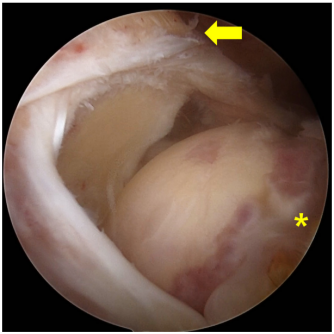

图1不可修复性后上肩袖撕裂的关节镜图像。撕裂的肌腱(箭头所示)已回缩至肩胛盂边缘,无法拉回至足迹处(星号所示)。